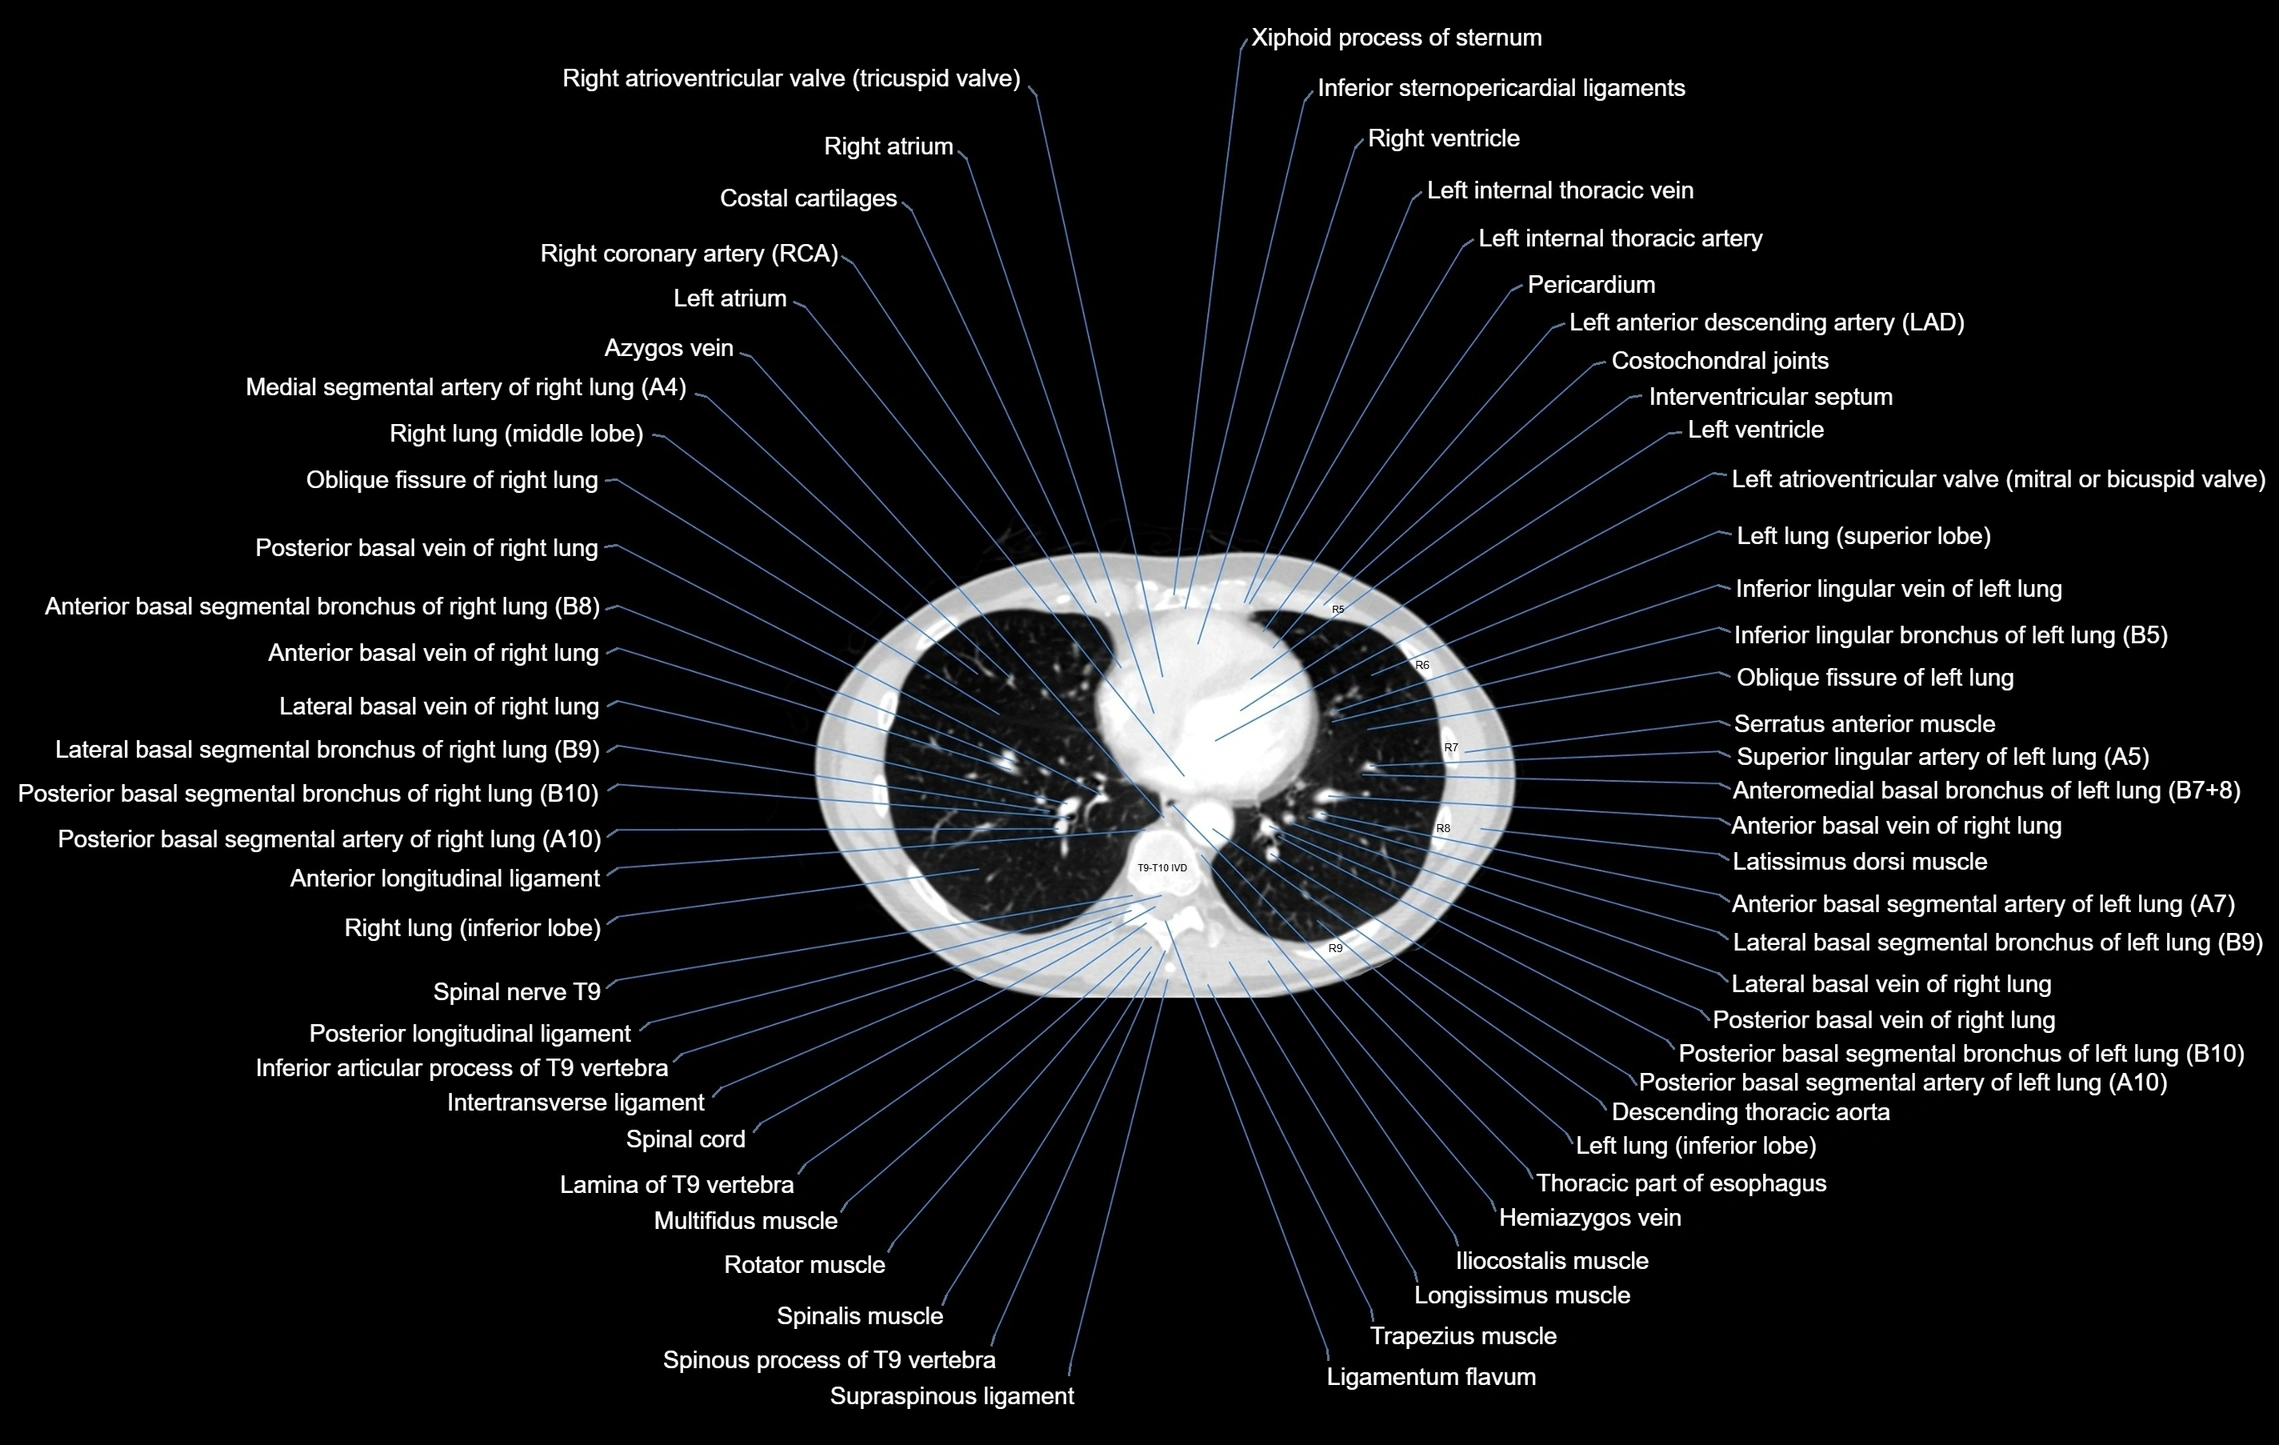

- T (Thoracic spine)